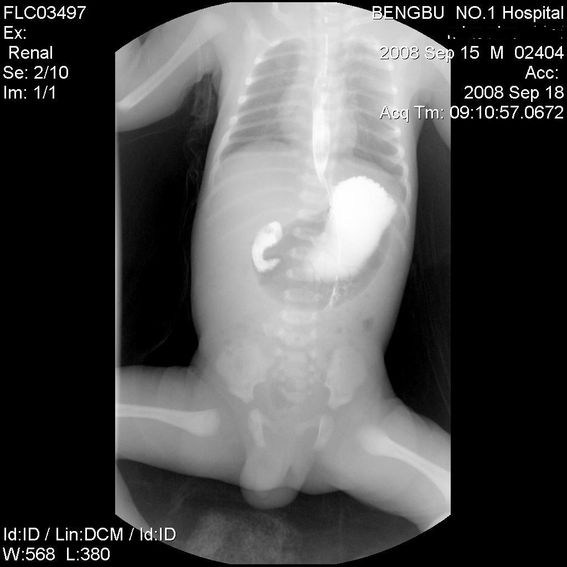

十二指肠降部钡流不能顺利通过,胃及十二指肠球扩张。

考虑----十二指肠降部狭窄-----〔但这几个片子狭窄未能清楚显示,无法判断分型-----膜性或管状〕

考虑----十二指肠降部狭窄

十二指肠降部钡流不能顺利通过,胃及十二指肠球扩张,符合十二指肠降部狭窄

符合十二指肠降部狭窄或扭转不良.